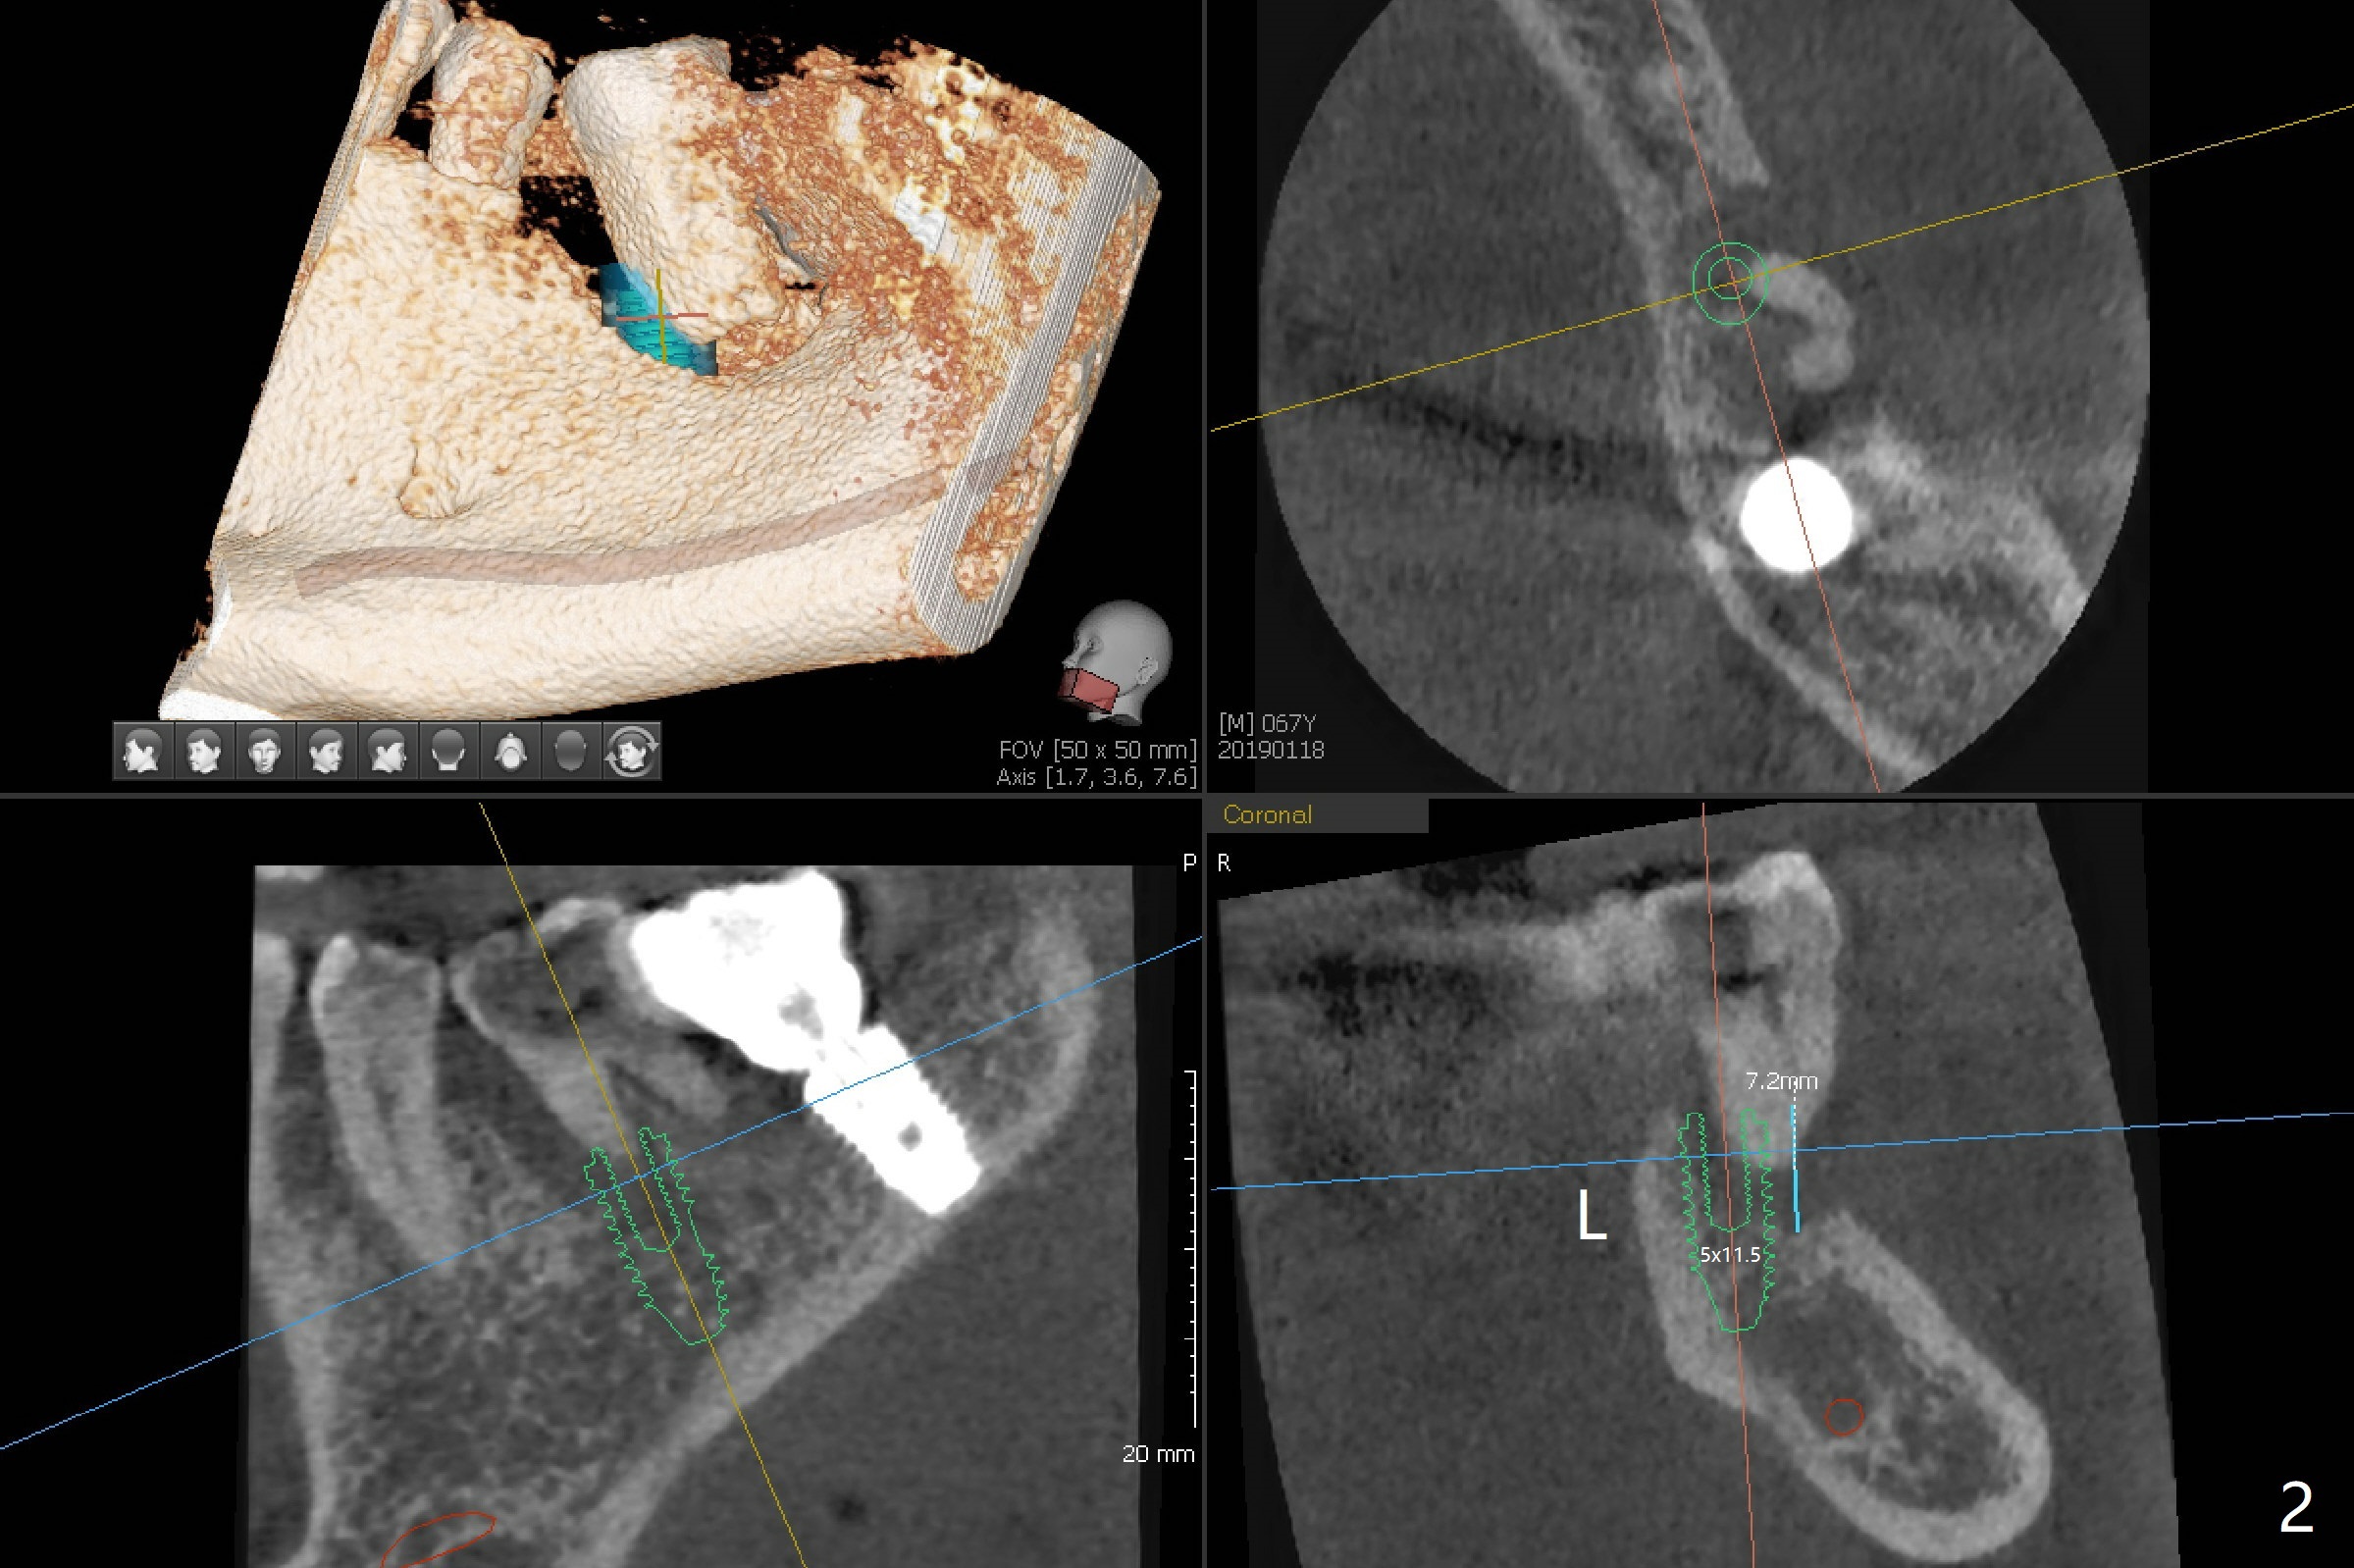

A 67-year-old man requests treatment for the tooth #19 with severe buccal gingival recession (Fig.1). After extraction, a 5x11.5 mm implant will be placed as lingual as possible (Fig.2 L) with ~7 mm buccal implant thread exposure. To reduce the exposure, the implant will be placed deeper, as shown by arrow in Fig.3. PRF membrane and collagen membrane (Fig.4 red line) will be placed against the buccal gingiva, while PRF associated sticky bone (allograft, pink circle) will be packed around the exposed implant threads and a long-cuff abutment (yellow). Finally an immediate provisional (Fig.5 white) will be fabricated to cover the bone graft.